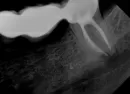

Разгерметизировался мост и воспалилась десна. Врач диагностировал трещину в зубе, а так же гной в десне под корнем зуба. Врач предложил удалять зуб, как единственное средство. Очень хочется сохранить зуб если не весь, то хотя бы половину.

Зуб необходимо удалить.

Поэтому удалить и поставить два имплантата в области зубов 5 и 7, и на них надеть мостовидный протез. Да, это дороже и дольше по времени, но зато надёжнее и на долгосрочную перспективу.